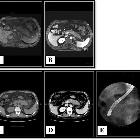

Pure

alpha-fetoprotein-producing neuroendocrine carcinoma of the pancreas: a case report. Imaging examinations. MRI showed enlargement of the pancreas body and tail with poor enhancement after gadolinium injection. Some enlarged peripancreatic lymph nodes were noted (A, B). Abdominal CT revealed diffuse enlargement of the pancreas body and tail, which appeared to be hypoattenuated with an unclear margin. A mass measuring 5.2 × 4.8 × 4.1 cm with probable encasement of the splenic vein was observed in the enlarged pancreas on contrast-enhanced CT (C, D). None of the imaging examinations revealed abnormal findings in the liver. The main pancreatic duct, common bile duct, and intrahepatic bile ducts were normal on endoscopic retrograde cholangiopancreatography (E).